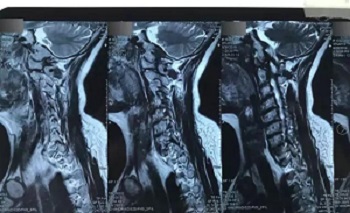

八、拍片子时,如果一张片子上有两张图像的时候,合起来拍一张,分开再各拍一张(如以下三张)

十一、将分区的磁共振图像,按顺序进行拍摄,即可获取如下比较有价值的清晰图片